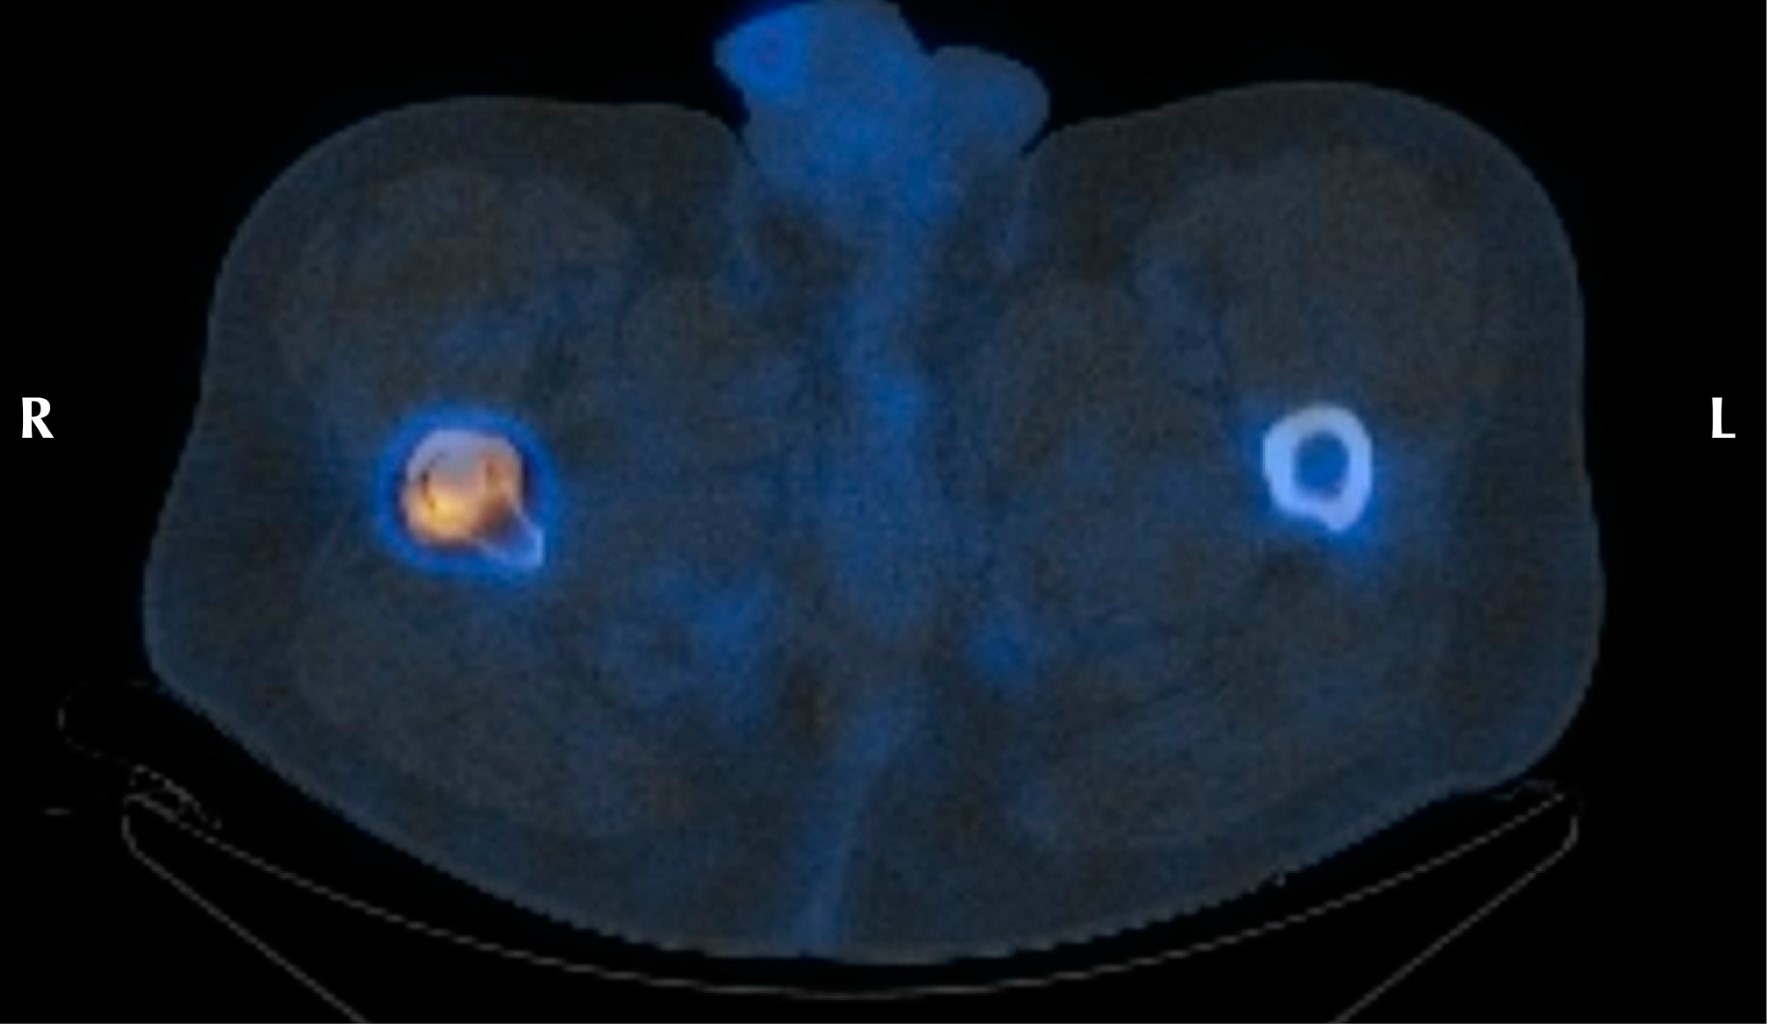

Minimizing risk: evaluation of the relationship between femoral stem loosening and the risk of presenting with peri-prosthetic hip fracture

Introduction: evaluation of predictors of periprosthetic fracture in loosened femoral stems. Material and methods: retrospective case-control study comparing aseptic loosened stems in two groups: cases: patients who experienced periprosthetic femoral fracture before replacement could be performed (n = 9). Controls: experienced prosthetic replacement without fracture (n = 19). Results: pain intensity (VAS) was the most important aspect (p = 0.01), predominating in the controls. The simple radiological parameters did not show statistically significant findings predictive of peri-prosthetic fracture (number of Gruen zones, sum of them in mm, stress shielding, pedestal, polyethylene wear, stem subsidence). The role of complementary tests (CT and scintigraphy) for the definitive diagnosis of loosening was relevant, but not significant. The type of implant showed no differences. Overall implant survival was higher in cases than in controls (p = 0.016). This difference continues when comparing each loosened stem until fracture or replacement (p = 0.024). Conclusion: the main factor protecting against fracture is the replacement of a stem with clinical and radiological diagnosis of loosening. Adequate follow-up of the patient plays a determining role in this, especially when considering the greater intensity of pain in the controls, which used to guide surgeons to perform replacements before the fracture occurred. This is reinforced if we take into account that up to one third of the cases did not have regular check-ups, and therefore did not have the opportunity for replacement prior to the fracture. The role of complementary tests (CT and scintigraphy) is also very important, taking into account the low diagnostic yield obtained from simple X-rays.

Figure 3